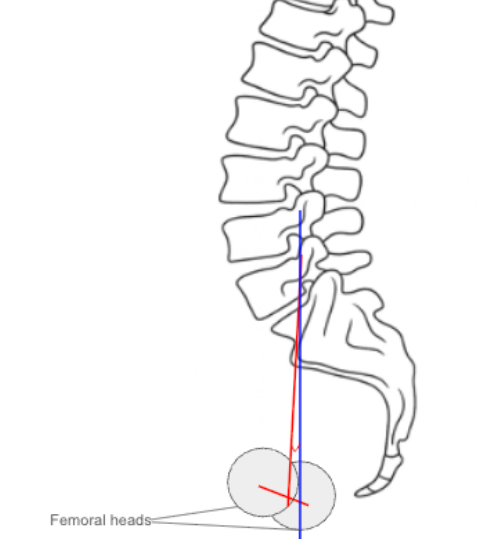

• Obtain a standing lateral lumbosacral X-ray with visualization of the femoral heads and sacrum.

• Identify two key anatomical landmarks:

• The center of the S1 endplate (midpoint of the superior sacral endplate).

• The center of the femoral heads (use the midpoint if both are visible).

• Draw a line connecting the center of the femoral heads to the center of the S1 endplate — this represents the pelvic axis.

• Draw a vertical reference line perpendicular to the horizontal plane.

• Measure the angle between the pelvic axis line and the vertical line — this is the Pelvic Tilt (PT).

• The angle opens posteriorly, increasing with pelvic retroversion.